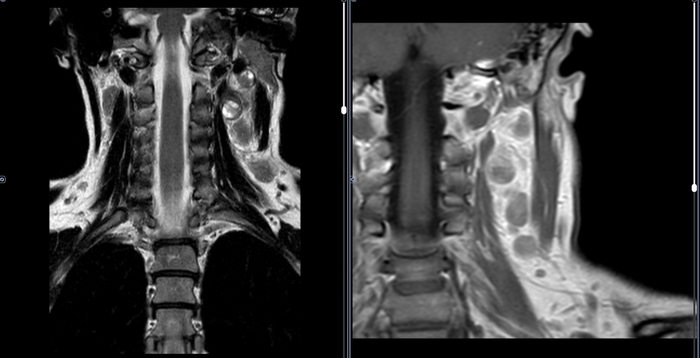

Изображения и частично текст взяли с радиопедии radiopaedia.org. 1 МРТ Т1, 2 МРТ Т2 (кейс 1), 3 - КТ с контрастом (кейс 2)

Магнитно-резонансная томография (МРТ)

Ключевой особенностью является высокая частота спонтанных кровоизлияний, что делает меланому одним из самых геморрагичных метастазов наряду с хориокарциномой.

Ключевые МР-признаки:

T1-ВИ: Обычно гиперинтенсивный сигнал (за счет меланина и/или крови).

T2-ВИ: Часто гипоинтенсивный.

T1-ВИ с контрастом: Контрастирование по периферическому (ободковому) или гетерогенному диффузному типу.